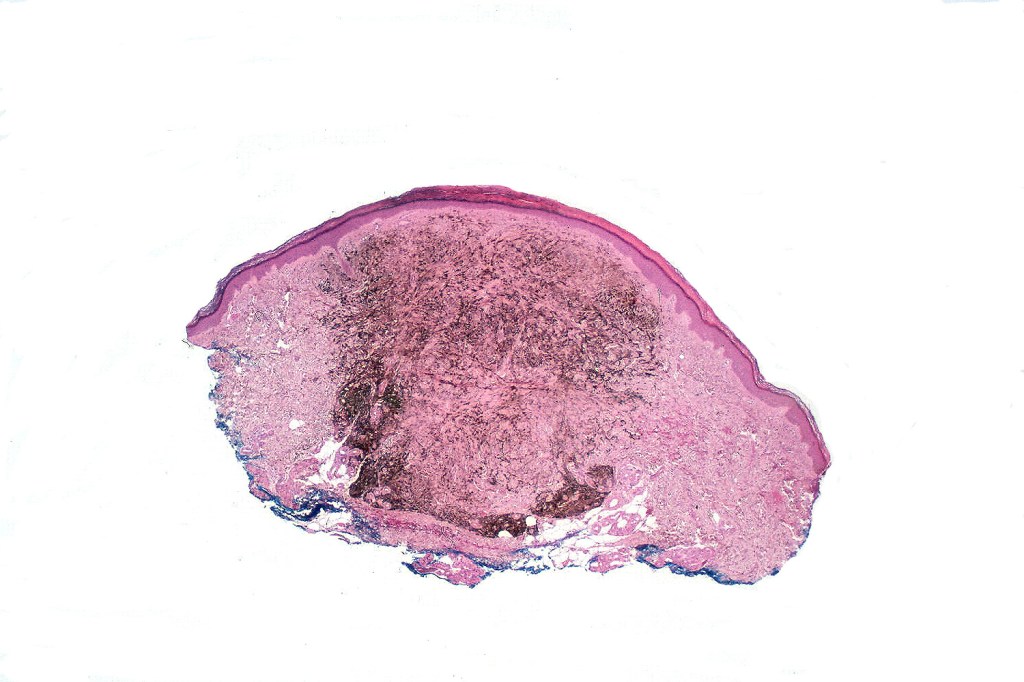

Cellular blue nevus

This uncommon most often devlops on the buttocks, sacrococcygeal region & distal extremities although it may be seen at just about any site. It shows a predilection for females and is diagnosed most often in the 2nd-4th decade. It presents as a blue-black/ or black nodule measuring 1-2 cm in dianeter. Similar to common blue nevus, the cellular variant can be encountered in a wide range of non-cutaneous locations.

•Most characteristic is the dumbbell silhouette although a plague morphology may also be encountered